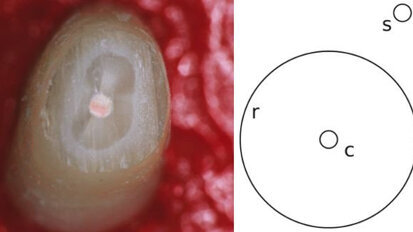

Cone Beam CT net zo effectief als standaard (micro-)CT-scan

AMSTERDAM – Een speciaal voor de tandheelkunde ontwikkelde Cone Beam CT-scan (CBCT) is net zo effectief in het analyseren van de microstructuren in ...